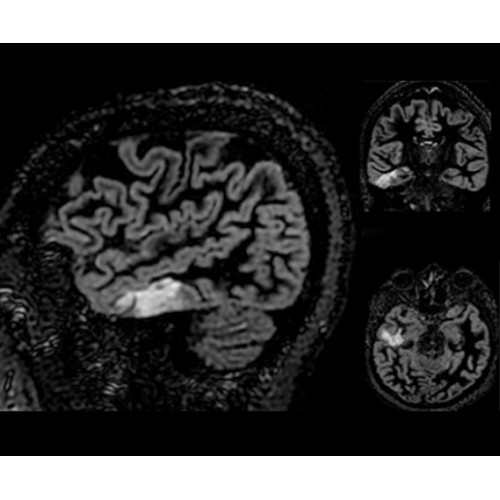

SIGNA PET/MR 3.0T — это гибридная система, в которой совмещаются две принципиально разные технологии — магнитно-резонансную томографию (МРТ) и позитронно-эмиссионную томографию (ПЭТ). Система отличающийся высокой чувствительностью и эффективностью и предназначена для диагностики в области онкологии, неврологии, кардио-васкулярных исследований, исследований воспалительных процессов.

Компания GE Healthcare представляет революционную, полностью интегрированную систему SIGNA PET/MR1, в которой сочетаются времяпролетная технология (TOF) и возможности напряженности магнитного поля 3.0 Тл. Мы поможем вам поднять исследования на более высокий уровень. SIGNA PET/MR позволяет достичь впечатляющей точности и скорости исследований, а благодаря новейшей технологии реконструкции Q.Clear2 качество изображений улучшается в два раза. Кроме того, в систему включен полный набор клинических приложений и гибких катушек для проведения любых видов исследования, открывая для вас возможности визуализации, о которых вы даже не догадывались.

Кроме того, в результате использования технологии TOF и инновационной технологии реконструкции Q.Clear вы сможете добиться прекрасного соотношения сигнал/шум. А благодаря технологии нулевого времени эхо (ZTE) визуализировать костную структуру без ионизирующего излучения. Все эти разработки для улучшения качества сканирования и точности анализа помогут вам использовать весь потенциал ПЭТ/МРТ.

• Q.Clear — в основу технологии легли накопленные знания о том, как минимизировать помехи при реконструкции и получить четкое изображение. При значительном улучшении качества изображения сохраняется точность расчетов. Сочетание технологии TOF и реконструкции Q.Clear — ваш надежный помощник для получения точных и достоверных данных.

• МРТ с функцией нулевого времени эхо (ZTE) отличается точностью, возможностью персональных настроек и отсутствием ионизирующего излучения. Она приходит на смену традиционному исследованию на основе рентгеновского излучения. МРТ с функцией нулевого времени эхо (ZTE) на базе SIGNA ПЭТ/МРТ является более надежной и быстрой по сравнению с системами, использующими сверхмалое время эхо (UTE).